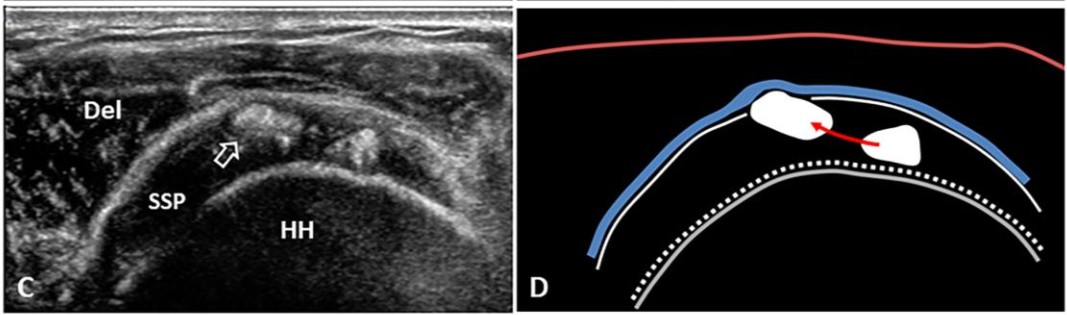

🖼 Hình SA-2 — Pha Resting: Short-axis SSP, vôi rắn hình arc, complete acoustic shadowing (Gärtner I, A,B)

Del=deltoid, Cor=coracoid, HH=humeral head, đường xanh=SA bursa, * = ổ vôi ellipse

SA Resting phase arc shadowing

🟢 Pha Resting (Vôi Rắn) — Hình Ảnh Siêu Âm

• B-mode: Vôi hình cung/ellipse, hyperechoic đồng nhất, bờ rõ, bóng lưng âm hoàn toàn che khuất cấu trúc phía sau. Gân dày khu trú, sợi gân bị đẩy ra hai bên.

• Short-axis: Vôi hình elipse/tròn, bóng lưng âm rõ; thấy bursal-side (mặt trên) và articular-side (mặt dưới) gân.

• Long-axis: Vôi dạng dải cong, gân phồng khu trú. Đo kích thước ở mặt phẳng lớn nhất.

• Doppler: Thường âm tính hoặc rất ít tín hiệu.

• Quét động: Khi dạng tay, ổ vôi va chạm mặt dưới dây chằng coracoacromial → tái hiện triệu chứng BN (xung đột cơ học có thể ghi lại được).